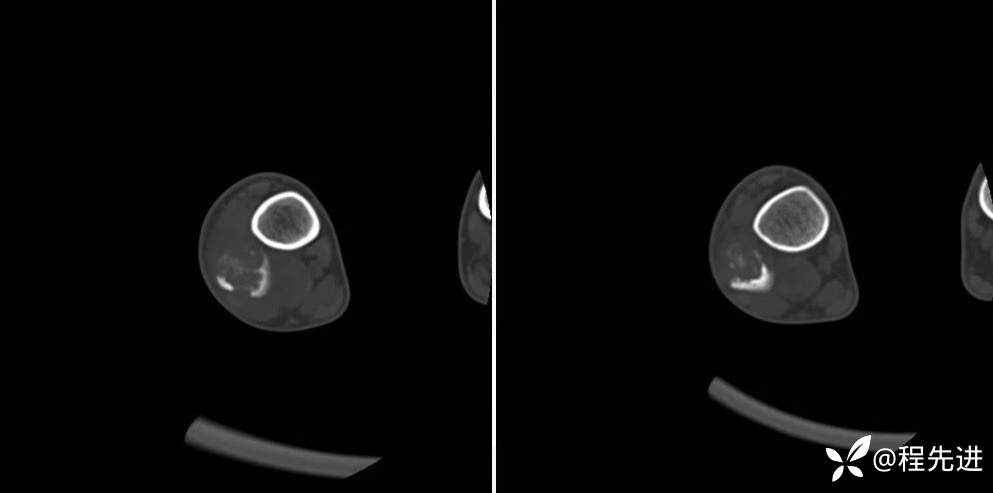

CT骨窗